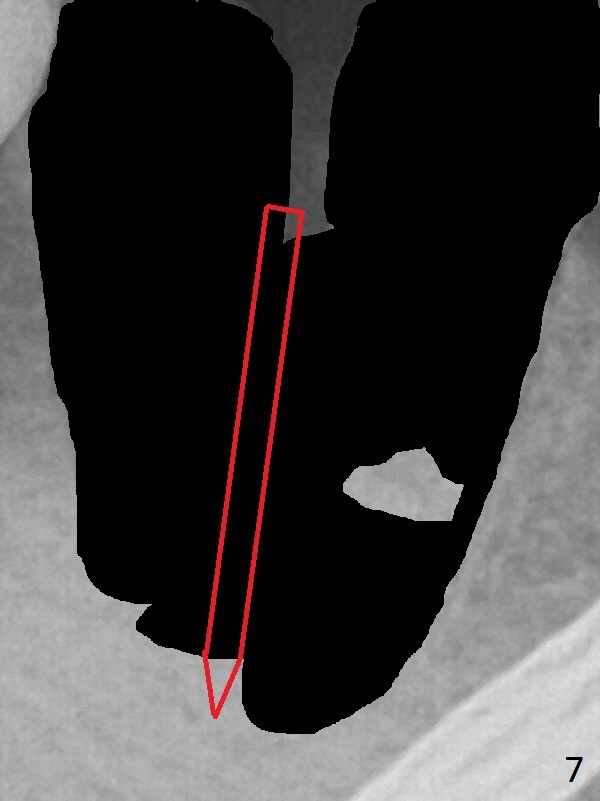

A 43-year-old man has residual roots at #30 (Fig.1). The mesial (M) and distal (D) roots approximates each other so close that the septum is thin (Fig.1,3-5). The latter is unfavorable for osteotomy. After extraction (Fig.5), the middle of the septum (Fig.8a (axial section of the sockets)) will be sectioned (Fig.6, 8b,c) prior to initial osteotomy (Fig.7,8d). The depth of the latter will be ~ 5 mm (Fig.2 red line) for a 13 mm (pink line) IBS implant.